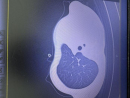

藏獒咬住老汉的一只手